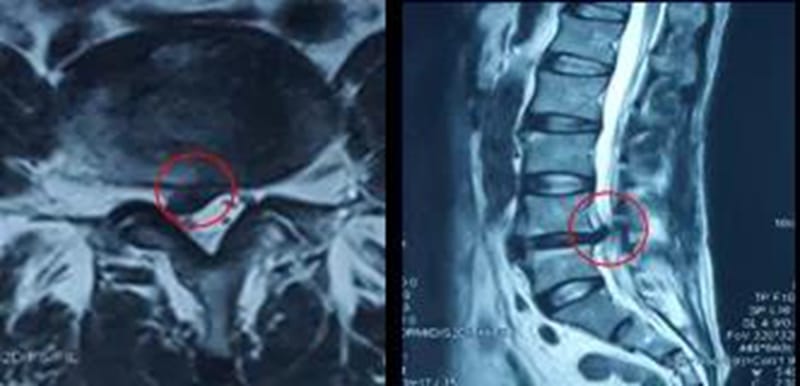

CT:鉴别有无椎间盘突出或突出方向

磁共振(MRI):显示椎管形态,椎间盘有无病变及神经根和脊髓受压情况,有诊断价值。